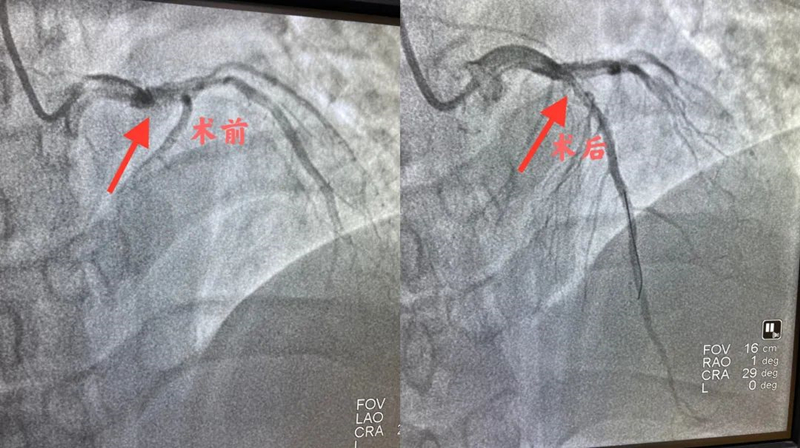

患者正值青壮年却发生了心肌梗塞,病情危重,于主任立即派科室医生及护士赶到急诊,上报医务科后开启了介入治疗绿色通道。患者不动,医护人员动,时间就是生命,时间就是心肌,在紧急与患者家属沟通介入治疗相关事项后,决定为患者行急诊冠脉造影检查。冠脉造影显示前降支近段100%闭塞,有效的治疗措施就是及时开通梗死动脉。于主任考虑此次心梗是由于患者原有血管狭窄基础上的急性闭塞所导致。于是与手术团队医生通过精准的操作,将闭塞血管成功开通。

一周后,经过心血管内二科团队的精心治疗,患者再次行冠脉造影显示前降支近段为70%狭窄,与患者及家属进行沟通,决定行冠脉FFR检查,进一步确认是否需要植入支架。FFR检测结果为0.86,暂无需介入治疗,次日患者康复出院。出院前,于主任叮嘱患者要注意休息,避免劳累,监测血压、血脂、血糖,定时服药。